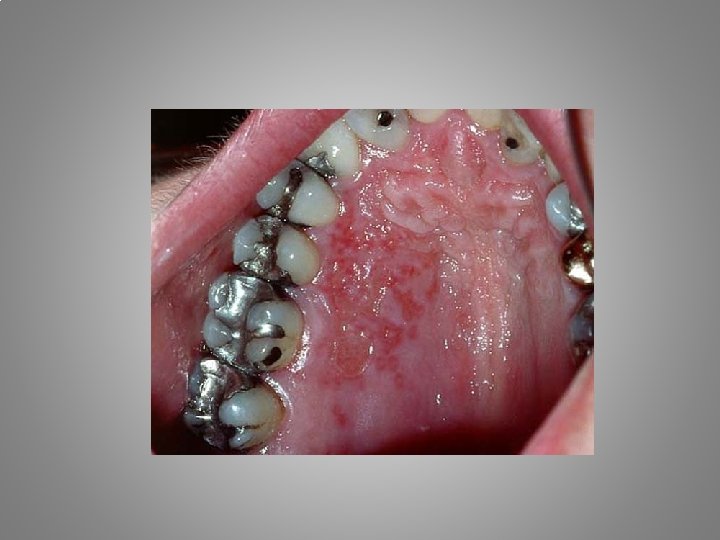

Types of orofacial pain Odontalgia : - Exposed dentin - Caries - Pulpitis - Apical periodontitis - Craced tooth sy. - Occlusal trauma - Periodontal abscessacute necrotising gingivitis - Periodontitis

Examination • Extraoral and intraoral inspectio. Signs of the inflammations. Tumor, calor, rubor, functio laesa. • Palpation of the laesion, lymphatic nodes, TMJ, periapical areas • Biting, cold, hot, percussion, bend forward